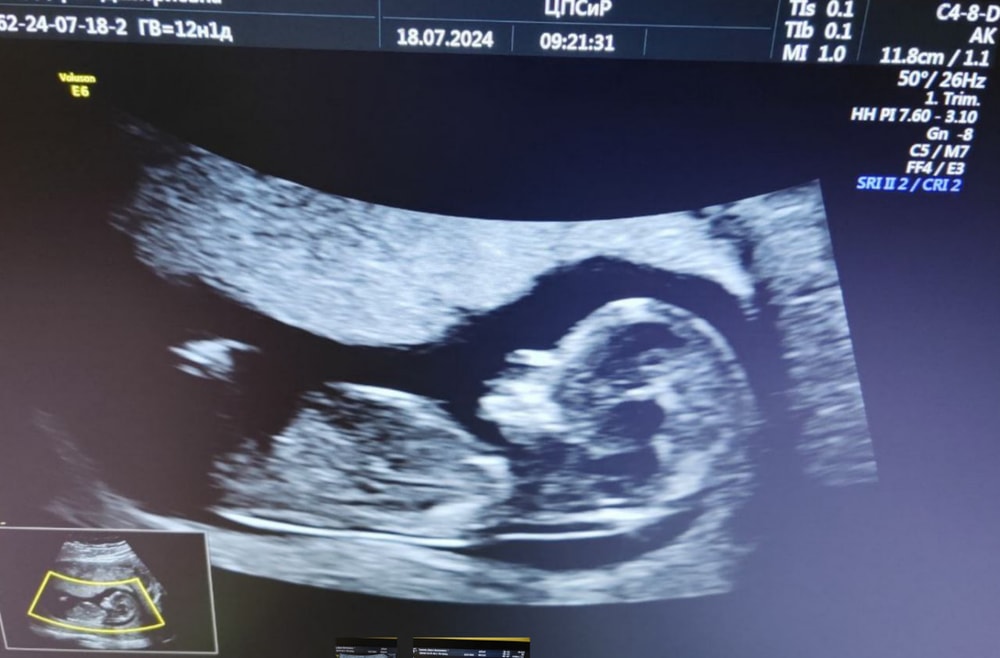

12 недель 1 день, первый скрининг (18.07.2024)

КТР 63мм, БПР (расстояние между висками) 21мм, ОЖ (объем живота) 69мм

Прикрепление хориона низко по передней стенке